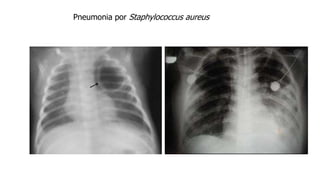

Pneumonia por Staphylococcus aureus

 Causa 1-2%das PACs  Importante causa de pneumonia durante ou após quadro de Influenza (Gripe)  Também se destaca entre as pneumonias adquiridas por via hematogênica  Muitas vezes os pacientes não têm doença de base  Potencialmente grave  Oxacilina sensíveis ou resistentes (MRSA) Staphylococcus aureus Escarro positivo para Staphylococcus aureus Mandell, Principles and Practice of Infectious Diseases, 8th ed., 2015